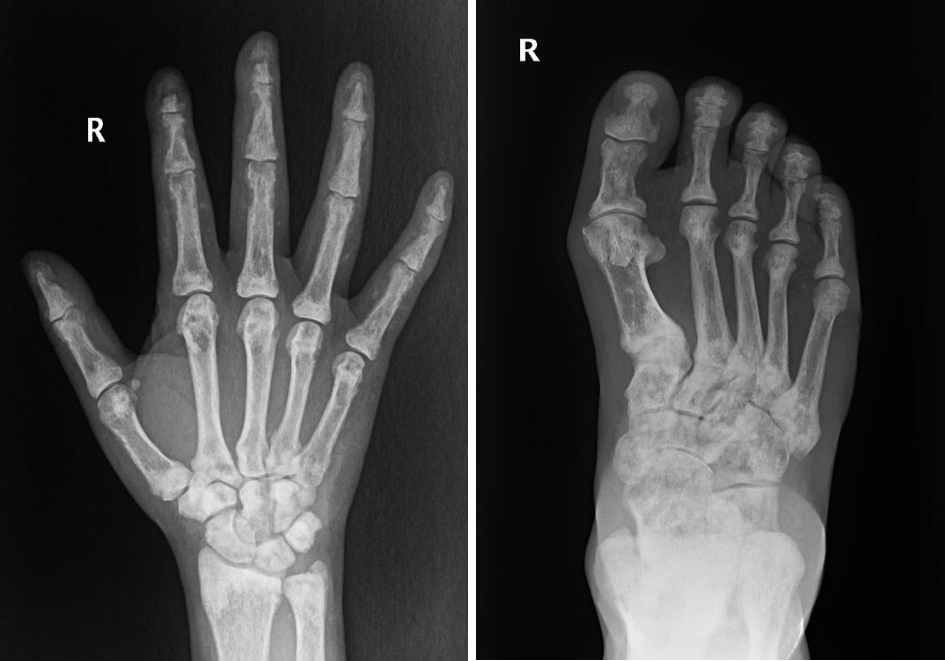

• 图2 患者手足X线检查 注:患者双手和双足骨质密度不均匀增高,双手部分远节指骨骨质吸收